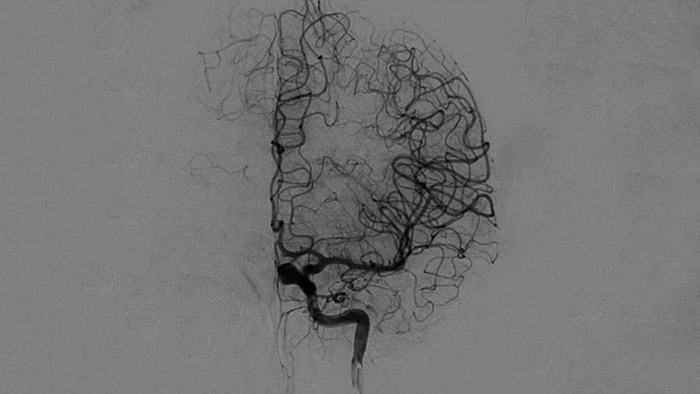

Imagens nítidas com DSA 2D com tecnologia ClarityIQ

DSA 2D com tecnologia ClarityIQ

O ClarityIQ aplica a compensação automática de movimento durante o DSA em tempo real para manter as imagens dos vasos nítidas. Isto suporta a tomada de decisões confiante ao longo dos procedimentos de acidentes vasculares cerebrais.

Confirme o sucesso do tratamento

Visualização de DSA

As visualizações de DSA de alta qualidade permitem avaliar se a recuperação completa do coágulo foi alcançada e se partes de coágulo foram dispersas distalmente no cérebro. Pode verificar a restauração do fluxo sanguíneo para a penumbra e verificar se existe hemorragia peri-procedimento.